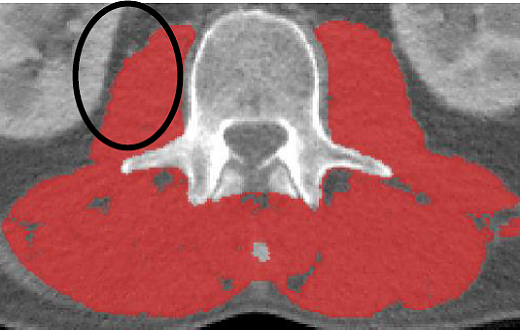

·For skeletal muscle analysis, all muscles at the L3 region will be analyzed (TAG 1- Red, HU Range: -29 to +150)

·Be careful not to include non muscle structures touching the psoas or other muscles